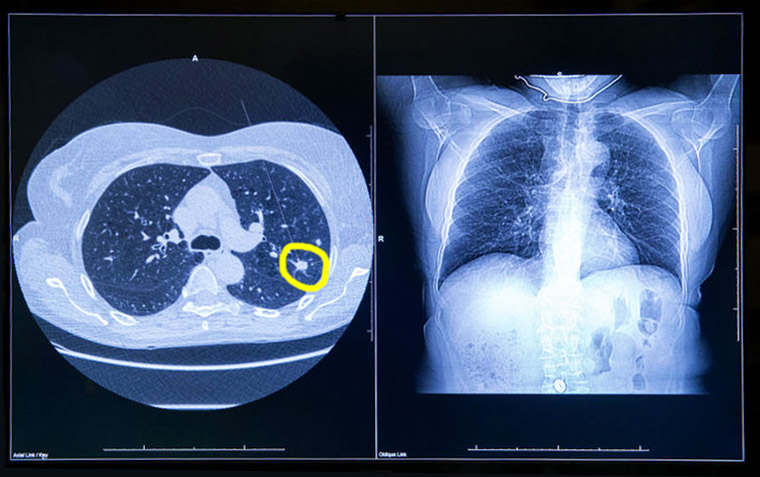

Sobrediagnóstico en el rastreo de cáncer de pulmón

En el estudio danés de tomografía computada de baja dosis para el cribado de cáncer de pulmón se halló que 2 de cada 3 casos detectados podrían corrresponder a sobrediagnóstico. JAMA Internal Medicine, 13 de agosto de 2018